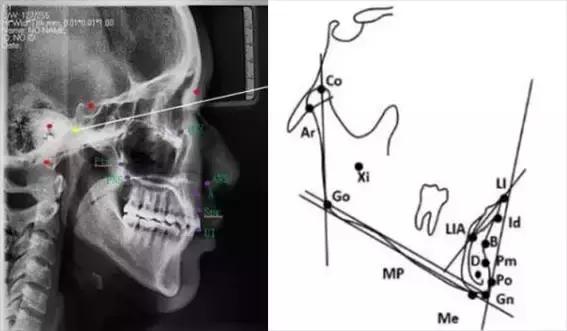

下颌标志点

髁顶点(Co.condylion):髁突的最上点。

关节点(Ar.articulare):颅底下缘与下颌髁突颈后缘之交点。关节点常在髁顶点不易确定时而代替髁顶点。

下颌角点(Go.gonion):下颌角的后下点。可通过下颌支平面和下颌平面交角之分角线与下颌角之相交点来确定

下齿槽座点(B.supramental):下齿槽突缘点与颏前点间之骨部最凹点。

下齿槽缘点(Id.infradentale):下齿槽突之最前上点。此点常在下中切牙之牙釉质-牙骨质界处。

下切牙点(Li.lower incisor):下中切牙切缘之最前点。

颏前点(P.pogonion):颏部之最突点。

颏下点(Me.menton):颏部之最下点。

颏顶点(Gn.gnathion):颏前点与颏下点之中点。

D点:下颌体骨性联合部之中心点。

这些标志点中,有些是在正中矢状面上,是单个的点。如鼻根点、蝶鞍点等。而有些则是双侧的点,如下颌角点,关节点等。若由于面部不对称而使两侧之点不重叠时,则取二点间的中点作为校正的位置。